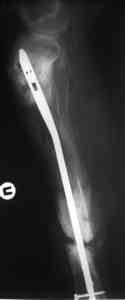

Пример (пациент 46 лет, лечился у нас 4 года назад, внутренний остеосинтез выполнен с определенными погрешностями, но перелом сросся и рецидива инфекции не было): рис. 1,2 - при переводе к нам в институт, рис. 3 - после микрохирругической пластики, рис. 4, 5 - после интрамедуллярного остеосинтеза, рис. 6, 7, 8 - внешний вид и рентгенограммы после окончания лечения

Штифт лучше взять неканюлированный, диаметр 10-11 мм. с большим количеством отверстий для блокирования (лучше ввести все блокирующие винты для создания максимальной стабильности).